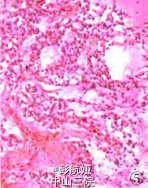

入院后行病理检查见右颈内静脉见癌栓,心脏扇扫显示左房占位,CT示肺内多数小点状阴影,考虑甲状腺癌转移,行左心房肿物切除术。术中见左房内肿物与房壁无关,肿物由肺静脉内长出,另见肺静脉内多发肿物。术中将左房内肿物送快速病理检查。眼观:肿物大小9 cm×7 om×5 cm,切面灰白色,黏液样,部分质韧,部分质软。镜检:黏液样物质背景下见肿瘤细胞呈梭形及圆形,呈团巢状、网格状排列,未见核分裂象。术中快速冷冻病理诊断:间叶源性肿瘤,部分区域细胞增生活跃,考虑肌源性可能性大。术后肿物行病理检查,镜下见肿瘤细胞呈梭形、圆形,细胞核较大,呈团巢状、网状排列,核分裂象少见,间质少,有大量粉染无结构物质,局部见大量坏死。免疫表型:vimentin、CK、TTF一1均(+++),Ki-67增殖指数<5%,Syn(灶状+),S-100、desmin、Myod.1、CR、HEMB一1、CKl9、SMA、p53、p63、Galectin-3、CK5/6、CK8/18、TG均(一),CT(+)(图4),刚果红染色:淀粉样物阳性

病理诊断:恶性肿瘤,结合病史及免疫表型考虑为甲状腺髓样癌转移癌栓。